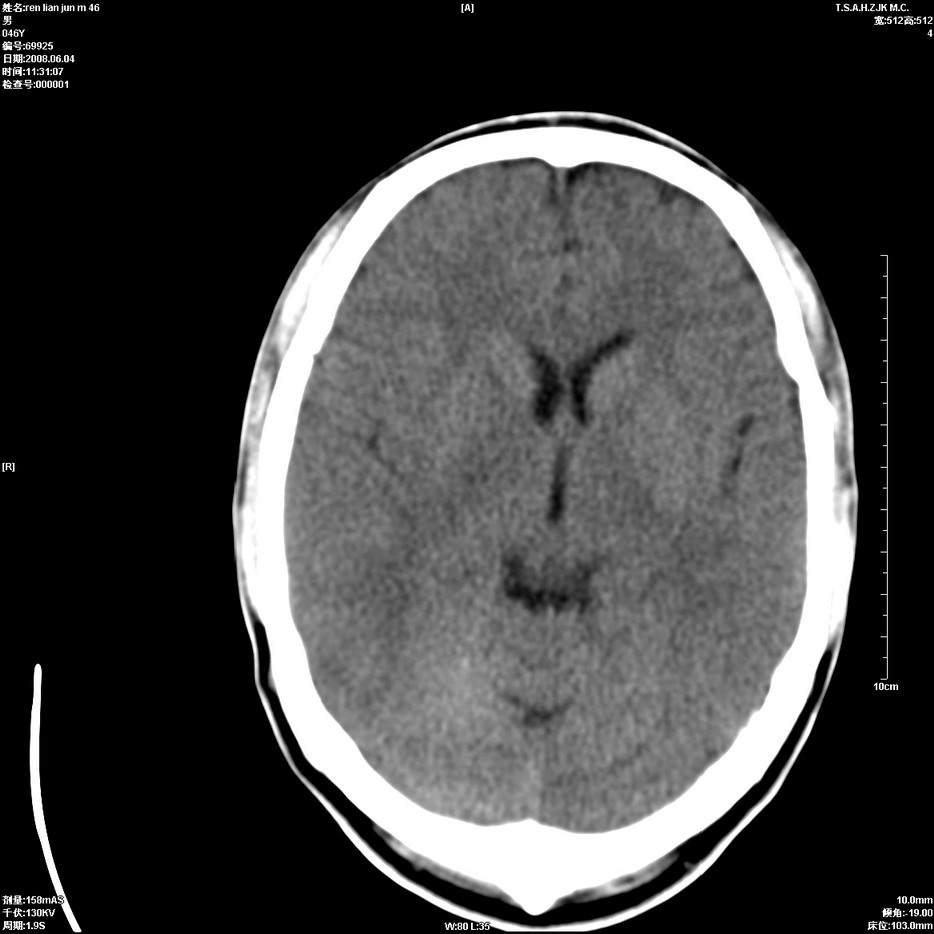

以下是引用qiu999在2008-6-5 17:14:00的发言:[br]考虑右肺中心型肺癌.颅内应做增强检查.

以下是引用形影不离在2008-6-5 19:18:00的发言:[br]右肺中心型肺癌并纵隔及左侧腋窝淋巴结转移,颅内应做增强检查。

以下是引用杀毒软件在2008-6-5 18:33:00的发言:[br]支持考虑右肺中心型肺癌,颅内病变是不是转移,不好说